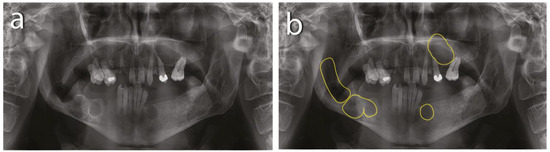

The intraoral examination revealed poor oral hygiene, with periodontitis, several missing teeth, and a few persistent roots. No visible manifestations of the cystic lesions in the oral cavity were detected. Panoramic radiographs and a CBCT scan revealed four cysts in both the mandible and maxilla (Figure 2). The first extensive radiolucent lesion spanned the right mandible from the condyle to the angle. A second, two-chamber osteolytic lesion was located in the right mandibular body in the molar area. Diagnostic imaging also revealed two cystic lesions in the left mandibular body in the premolar area and another in the maxilla, which was located between teeth 24 and 26 and was pushing their roots away from each other. The preparation for surgery consisted of scaling, a periodontic treatment, and dental sanation.

Figure 2. Preoperative CBCT scan: (a) maxillar keratocyst in the left upper region; (b) keratocysts in the mandible.